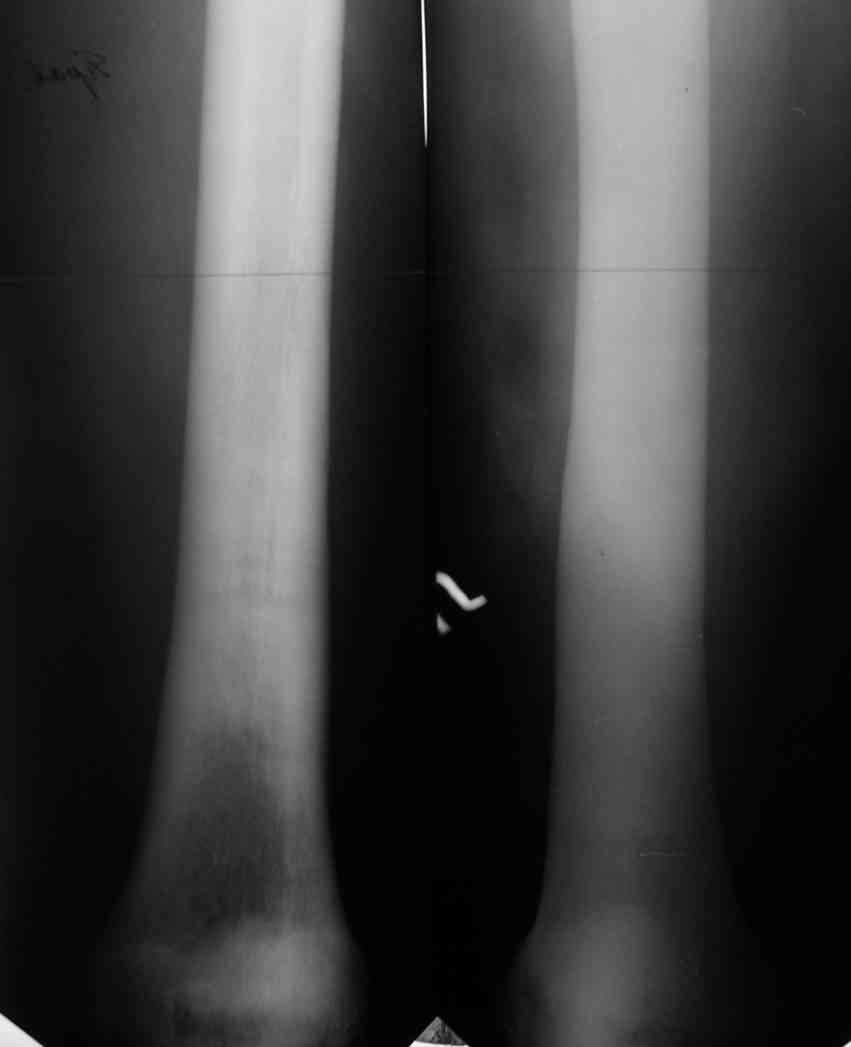

Уважаемый Константин Иванович! Полностью согласен с проф. Михайловым, данный случай не похож на мраморную болезнь, при которой имеется резкое, строго симметричное и генерализованное уплотнение костной ткани (остеопетроз), и кость оказывается построенной преимущественно из гомогенного компактного костного вещества. Для примера привожу случай из архива нашего института (бедренные, плечевые кости и таз, рис 1,2,3)

Изменения структуры костей у Вашего пациента больше похожи на полиоссальную форму фиброзной дисплазии или болезнь Педжета, возможены также инфаркты костного мозга б.берцовых костей. К сожалению, качество снимка не очень хорошее, непонятно, сохранен ли кортикальный слой б.берцовых костей по передней поверхности.